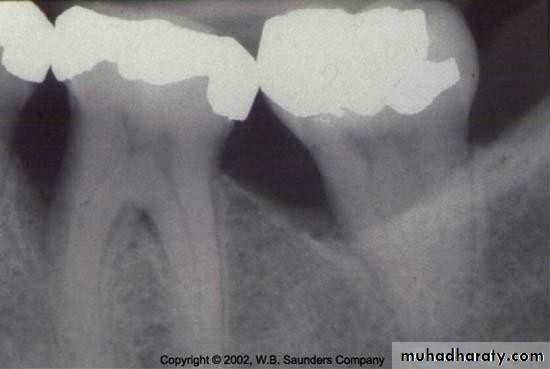

• Periodontal Examination

• Radiographic Assessment• Periodontal Examination

• Radiographic Assessment• three-wall vertical defect

• two-wall vertical defect

• one-wall vertical defect